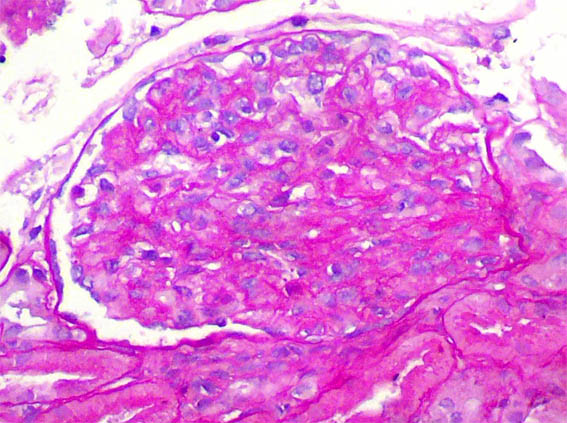

Figura 3.

PAS, X400.